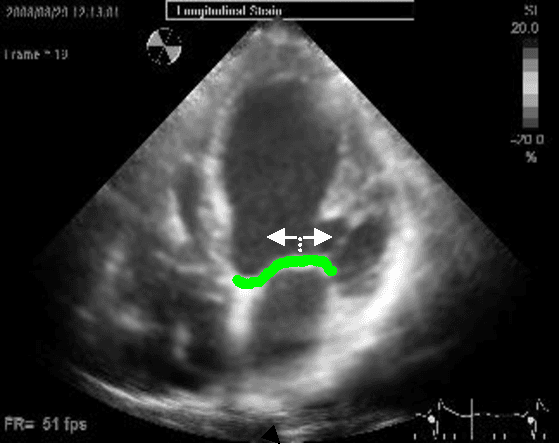

Abstract:Left ventricular segmentation is essential for measuring left ventricular function indices. Segmentation of one or several images requires an initial guess of the contour. It is hypothesized here that creating an initial guess by first detecting anatomical markers, would lead to correct detection of the endocardium. The first step of the algorithm presented here includes automatic detection of the mitral valve. Next, the apex is detected in the same frame. The valve is then tracked throughout the cardiac cycle. Contours passing from the apex to each valve corner are then found using a dynamic programming algorithm. The resulting contour is used as an input to an active contour algorithm. The algorithm was tested on 21 long axis ultrasound clips and showed good agreement with manually traced contours. Thus, this study demonstrates that detection of anatomic markers leads to a reliable initial guess of the left ventricle border.